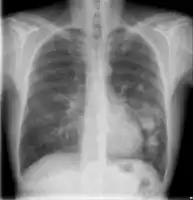

| Top: Superficial oral candida Bottom: Systemic aspergillosis pneumonia | |

Systemic

Systemic fungal infections include histoplasmosis, cryptococcosis, coccidioidomycosis, blastomycosis, mucormycosis, aspergillosis, pneumocystis pneumonia and systemic candidiasis.[4] Opportunistic systemic fungal infections include candidiasis, cryptococcosis and aspergillosis.[4]

-

.jpg) Chest X-ray: Angioinvasive aspergillosis

Chest X-ray: Angioinvasive aspergillosis -

Chest X-ray of lungs affected by cryptococcosis

Chest X-ray of lungs affected by cryptococcosis -

Chest X-ray of lungs affected by histoplasmosis

Chest X-ray of lungs affected by histoplasmosis -

![X-ray of cyst in pneumocystis pneumonia[17]](./_assets_/0c70a452f799bfe840676ee341124611/X-ray_of_cyst_in_pneumocystis_pneumonia_1.jpg) X-ray of cyst in pneumocystis pneumonia[17]

X-ray of cyst in pneumocystis pneumonia[17]